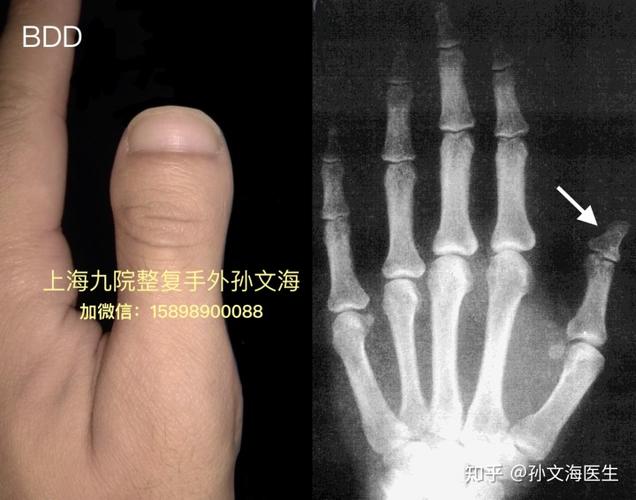

第四脚趾短小症手术

第四脚趾短小症手术,第四脚趾短小症

第四足趾短小短趾症

转载 第四跖骨短小症(单足典型病例)

e 掌骨短小,指骨长度正常(e1: 第四跖骨短小症) 图1.